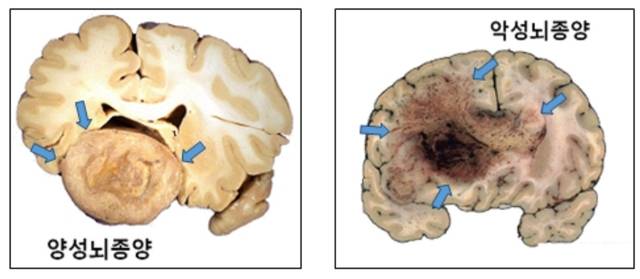

뇌종양은 조직학적 특성에 따라 양성과 악성으로 나눈다. 양성 뇌종양은 성장속도가 1년에 1~2㎜ 미만으로 느리다. 증상이 있거나 주기적으로 MRI를 촬영하며 관찰하다가 성장 속도가 일반적인 경우보다 빠르다고 판단 될 때 치료를 고려해도 늦지 않다. 대표적인 양성 뇌종양에는 뇌를 둘러싼 수막에서 발생한 뇌수막종, 뇌의 정중앙부 하단에 위치한 ‘뇌하수체’에서 발생한 뇌하수체 선종, 뇌신경에서 발생하는 신경초종이 있다.

반면 악성 뇌종양은 진행이 빠르고, 성장하면서 뇌조직을 침범하는 경향을 보인다. 대표적으로 뇌교종은 뇌신경세포를 지지하는 교세포에서 발생하며, 절반 이상이 악성이다. 양성 뇌교종도 시간이 지나면서 악성화되는 경우가 많다. 뇌교종이 발견되면 일부 예외적인 경우를 제외하고, 대부분 증상이 없더라도 치료가 필수적이다. 교모세포종은 뇌교종 중에서도 발생 빈도와 악성도가 가장 높은 치명적인 유형이다. 국내에서 연간 800여명의 환자가 발생한다. 치료받지 않을 경우 평균 생존 기간은 3~6개월이다. 치료 시 약 1년이 연장된다. 교모세포종이 아닌 악성 뇌교종도 핍지교종을 제외하고는 불량한 예후를 보이는 경우가 많다.